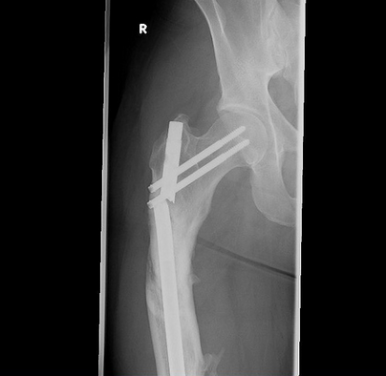

GET THE LATEST BREAKING NEWS HERE -- SIGN UP FOR GOLOCAL FREE DAILY EBLASTThe surgeries that had the highest adjusted complication rates were knee replacements, hip replacements and lumbar spinal fusions -- which according to ProPublica, one of the most common reasons for the surgery “is the narrowing of the space between the vertebrae, which puts pressure on the spinal cord and nerves, causing pain. It can also be done because of disc degeneration or a condition where one bone in the back slides forward over the bone below it.”